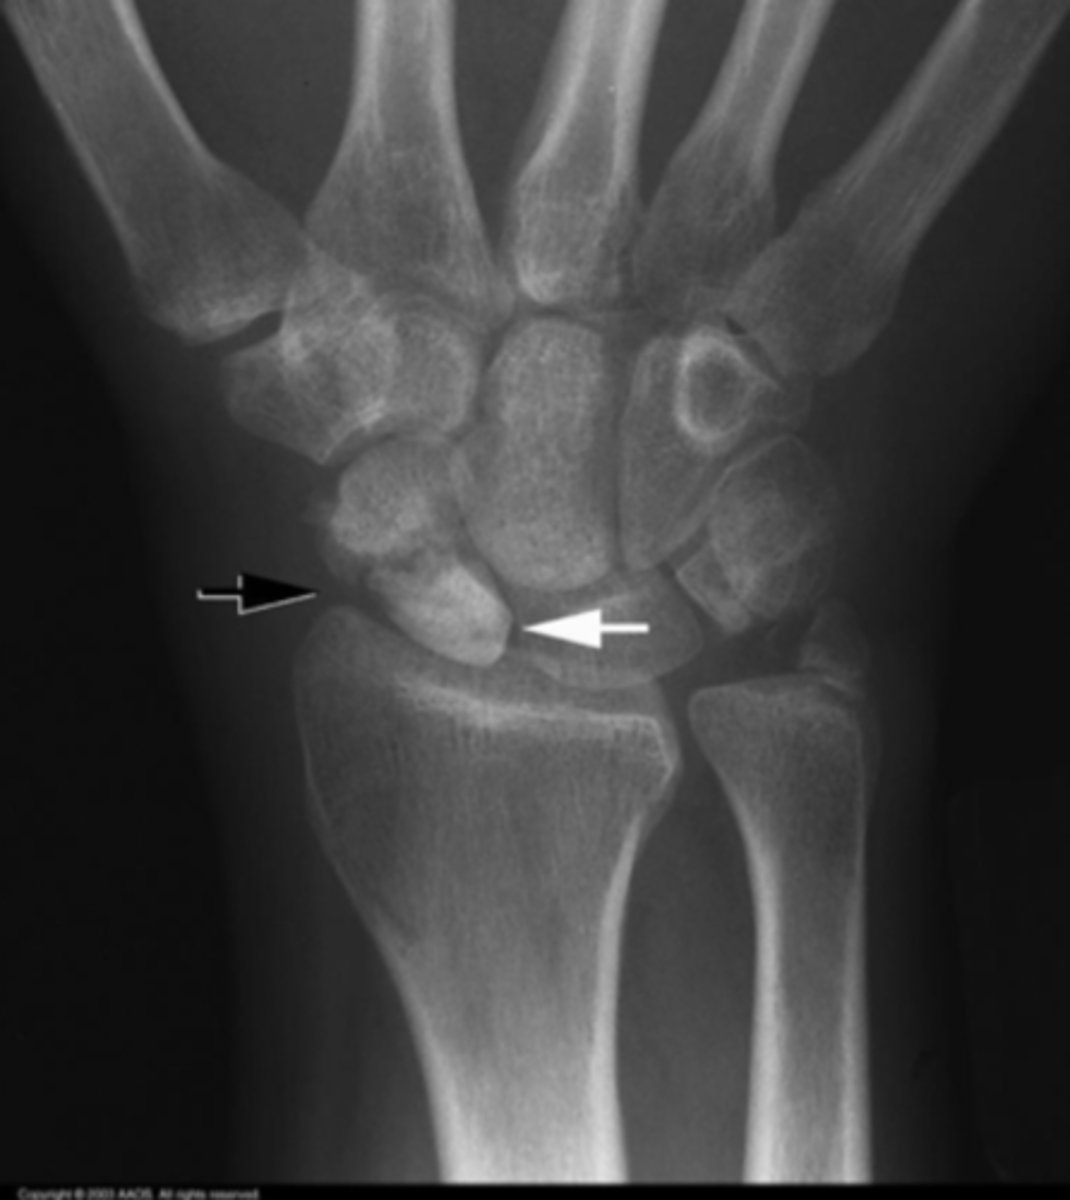

Scaphoid fracture and minor ulnar fracture

What is the issue?

Scaphoid fracture